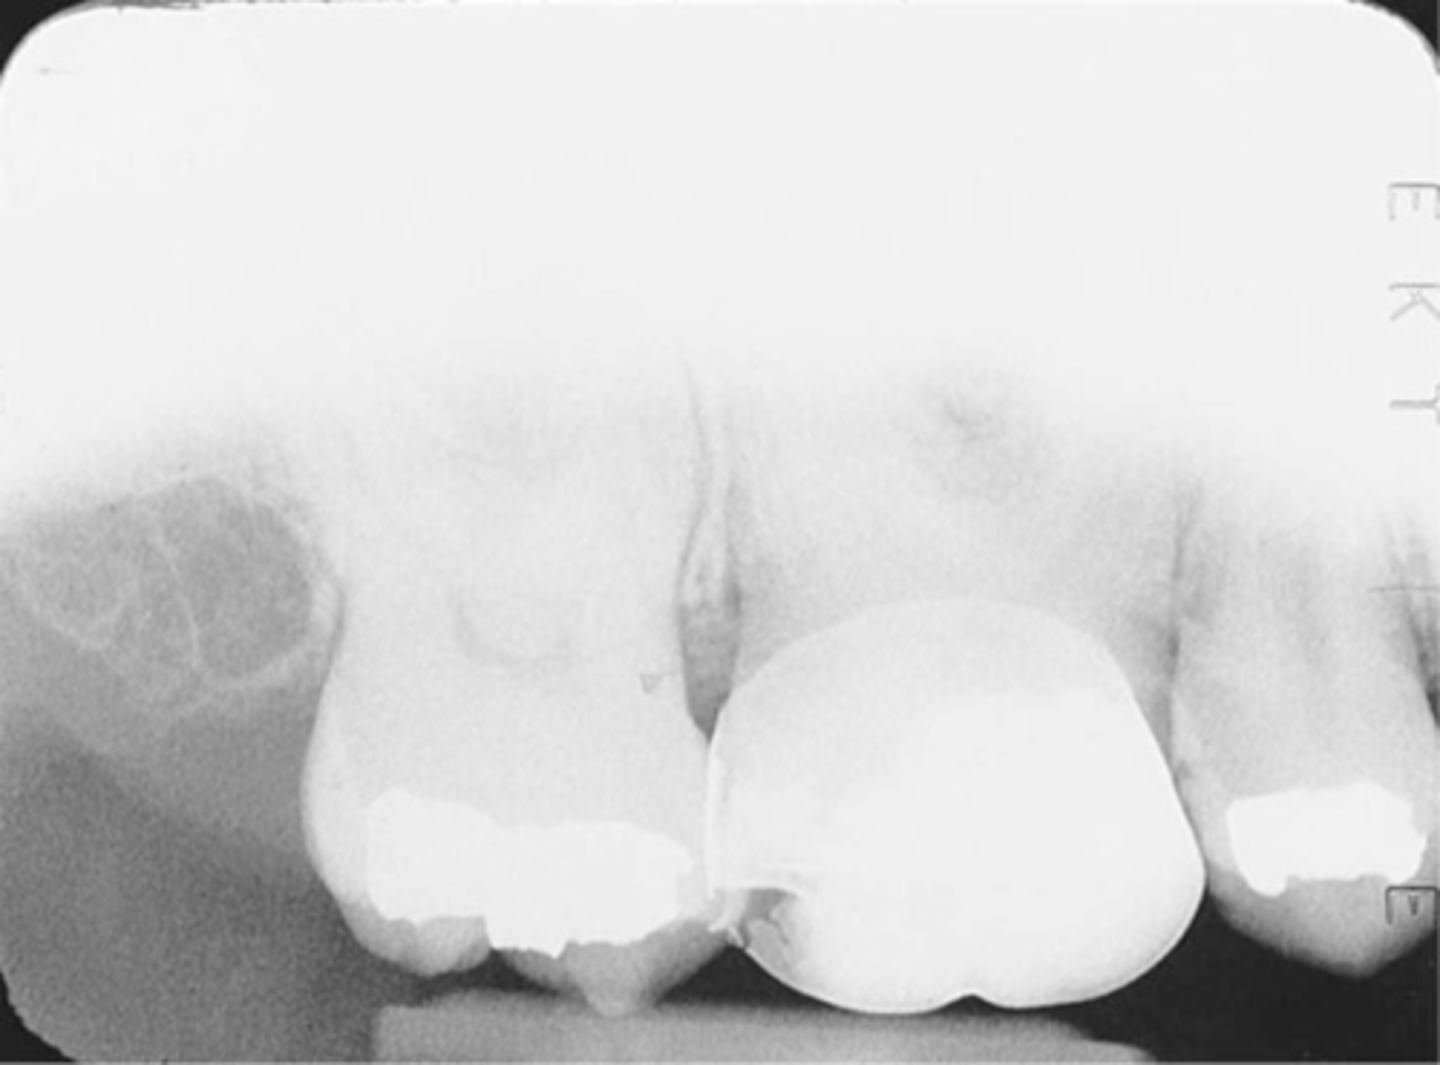

Incorrect Receptor Placement--Premolar Bite-Wing

-Distal surfaces of canines are not visible on the image

-Receptor was positioned too far posteriorly in the mouth; front edge of the receptor was not placed at the midline of the mand. canine.